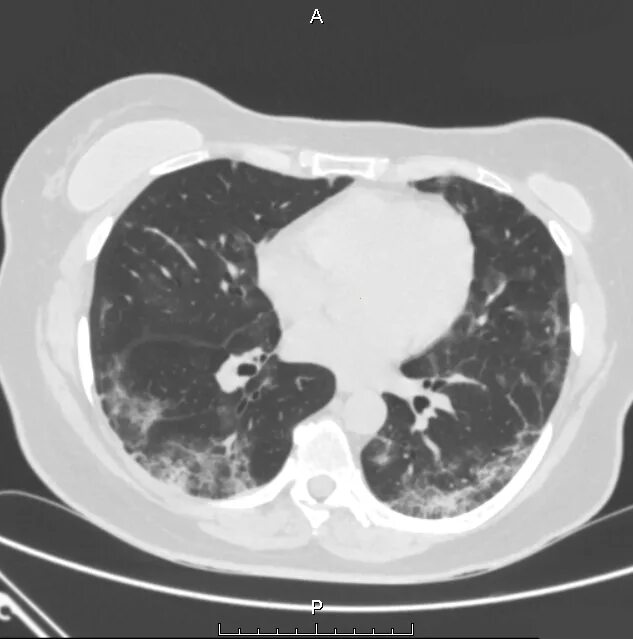

Аортокоронаросклероз легких что это такое